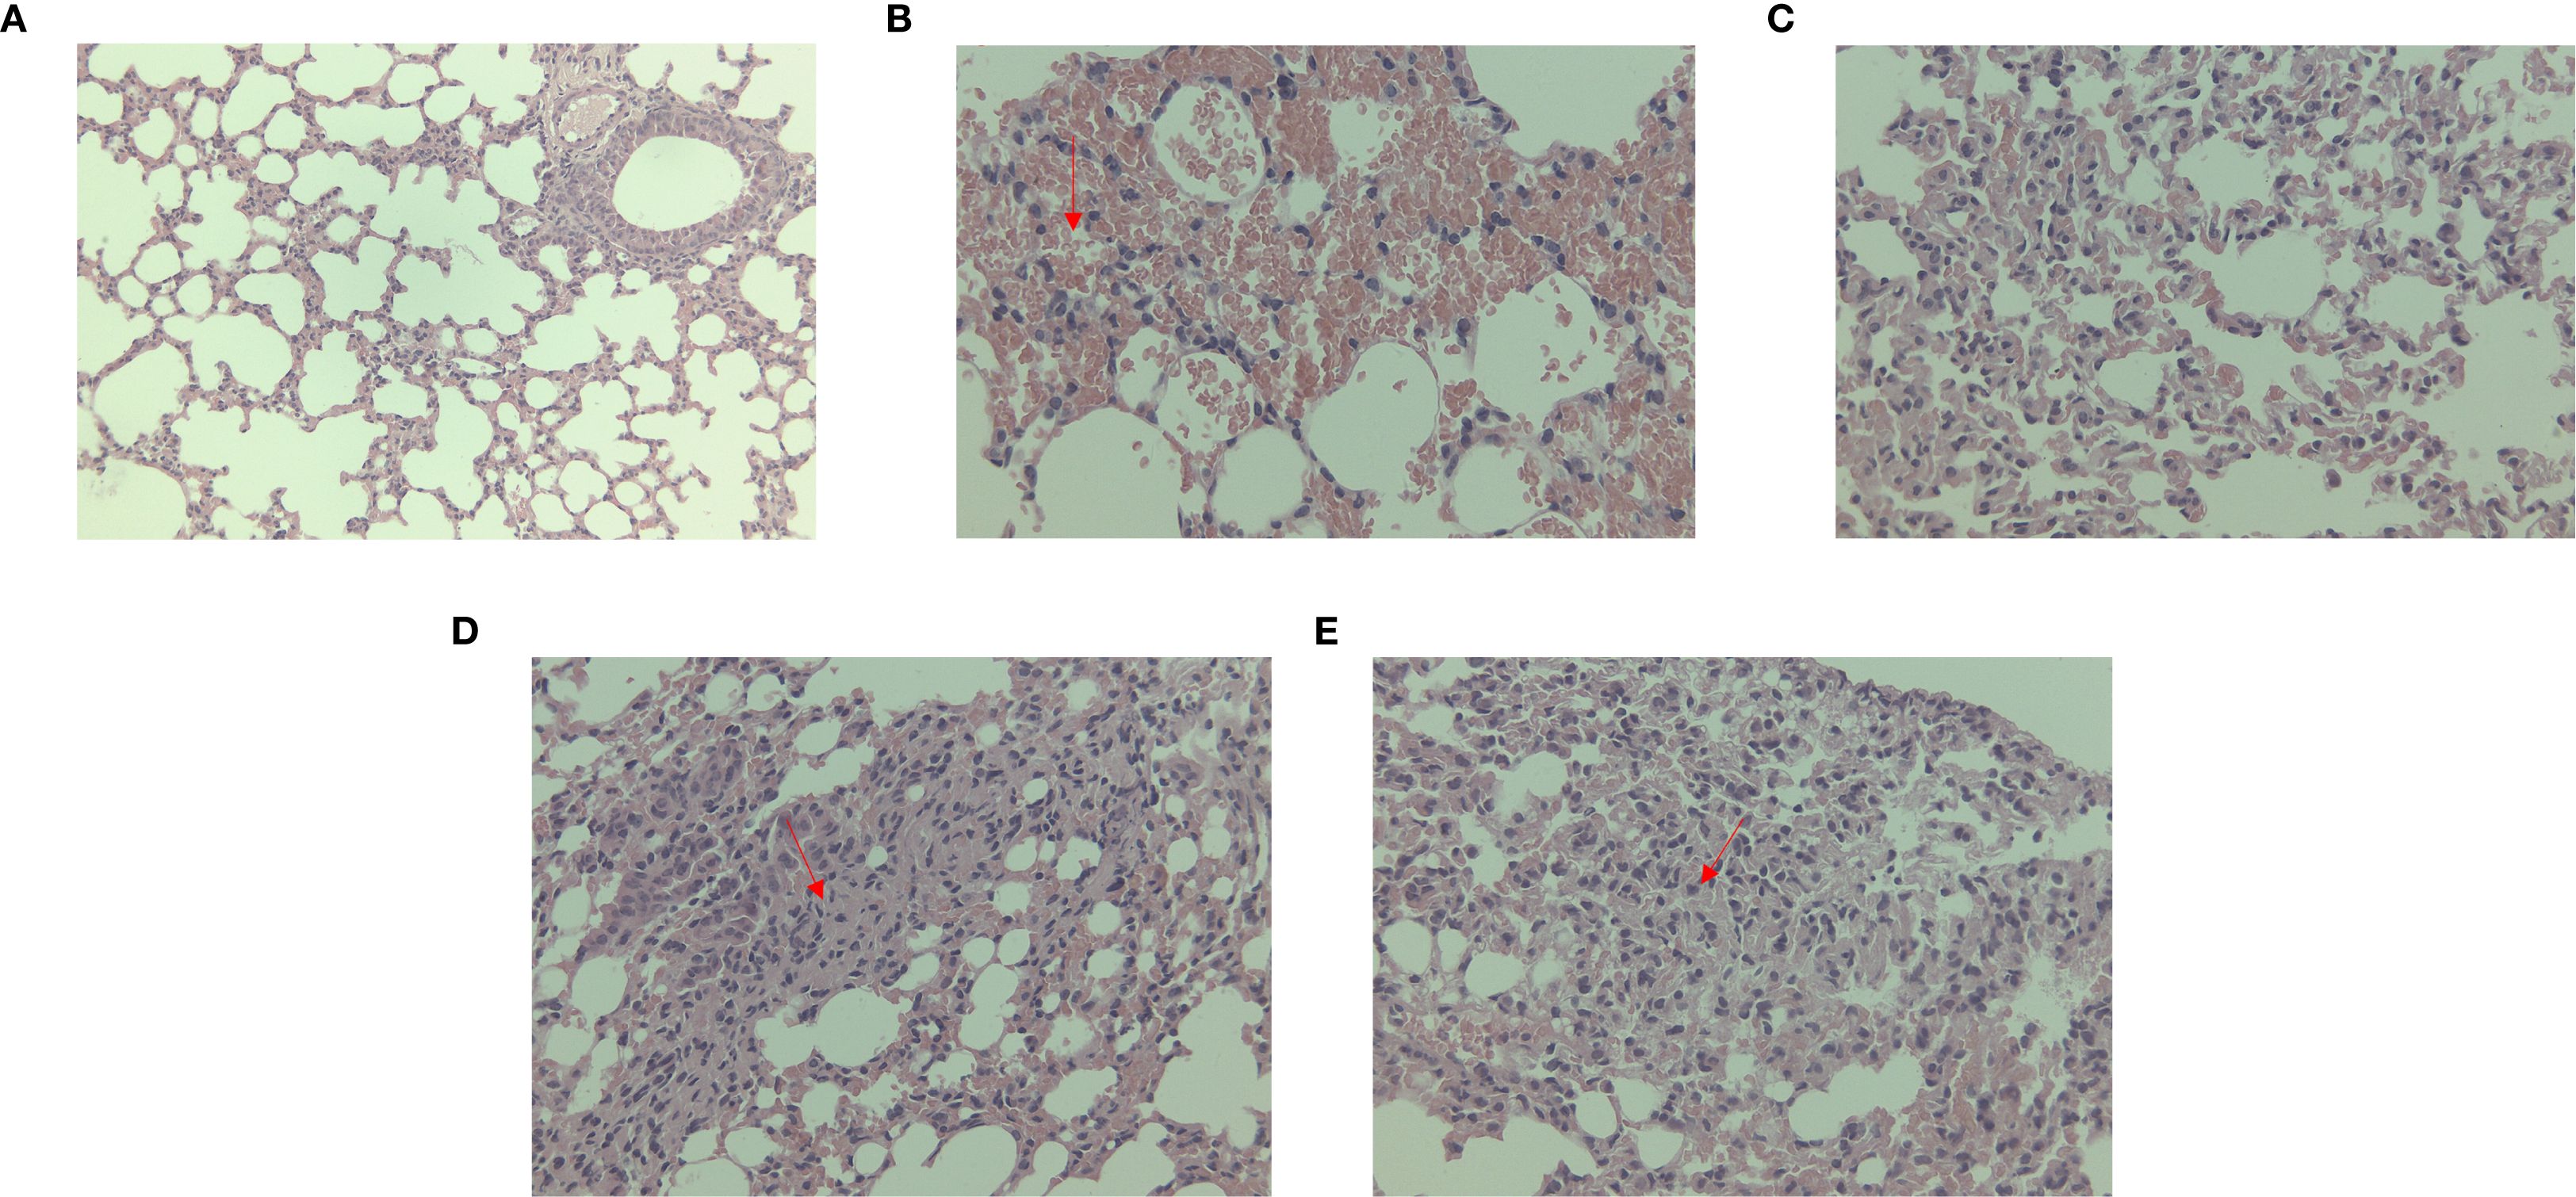

Under microscopic observation, severe consolidation lesions were observed in the C. psittaci+E. faecalis group and C. psittaci/E. faecalis group, diffuse hemorrhagic inflammation was evident in the lungs of the C. psittaci alone group, and no obvious lesions were found in the E. faecalis alone group (Figure 8).

Figure 8. Lung lesions after coinfection with Chlamydia psittaci and Enterococcus faecalis in mice under microscopic observation. (A) Control group, (B) C. psittaci alone group, (C) E. faecalis alone group, (D) C. psittaci+E. faecalis group, and (E) C. psittaci/E. faecalis group.